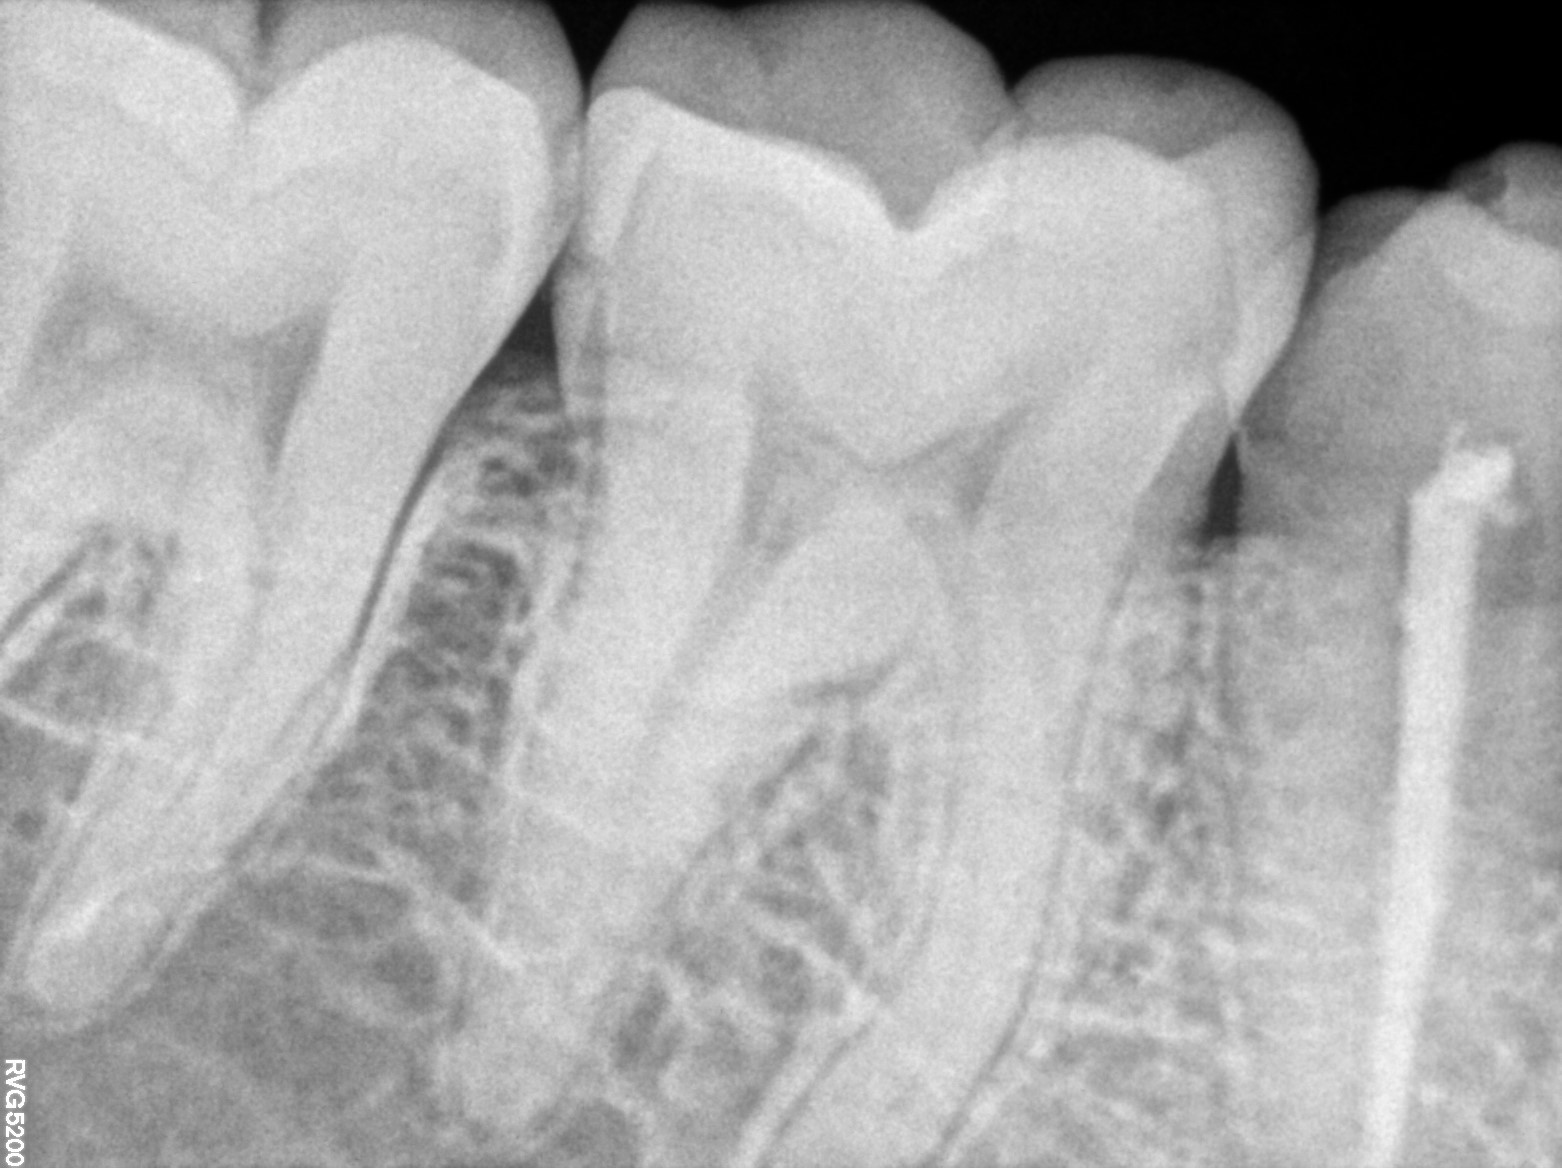

Dental Radiographs FHIR: DocumentReference · LOINC 24641-7

FHIR Bundle

xray_1772642539_0.jpg

24641-7

xray_1772642477_1.jpg

R55.jpg

xray_1770998647_1.jpg

R57.jpg

xray_1770476620_0.jpg

xray_1770998647_0.jpg

xray_1771259343_0.jpg

R56.jpg

xray_1772120353_0.jpg

R62.jpg

xray_1772642477_0.jpg